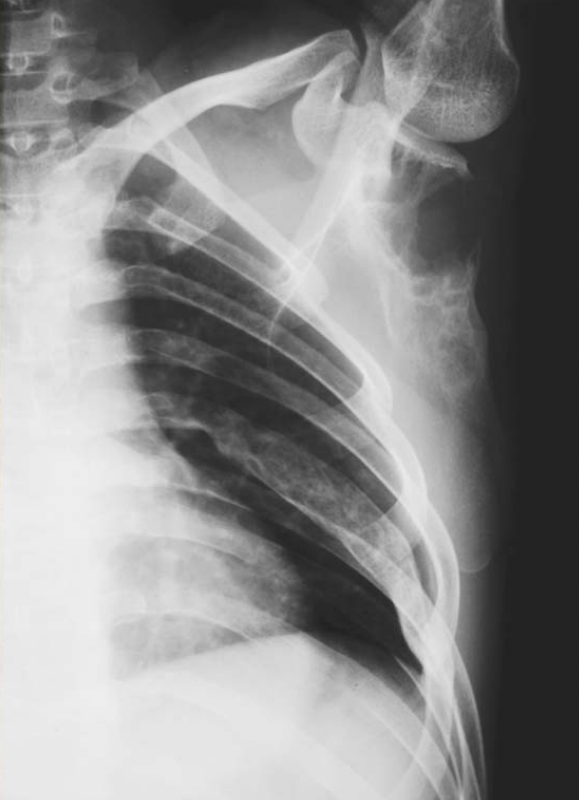

Figure1